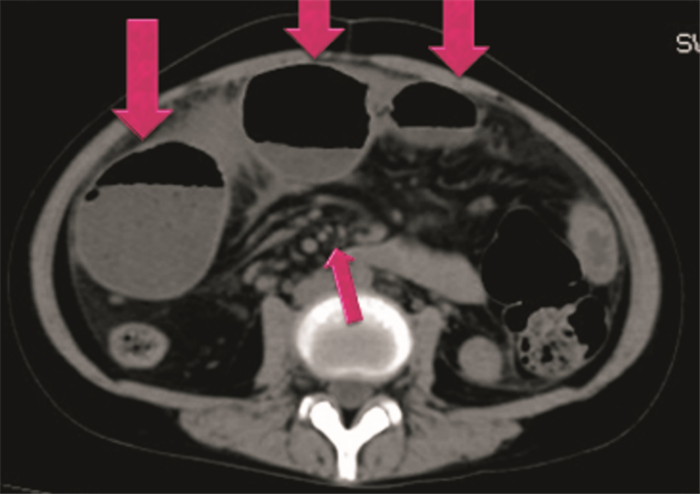

患者女,19岁,主因“间断腹痛1个月,加重2 d”于2016年9月19日入院。患者1个月前无明显诱因出现腹痛,自诉疼痛位置不定,主要为右下腹及脐周胀痛,偶伴恶心,无呕吐,于卫生部中日友好医院门诊就诊,完善腹部超声未见明显异常,妇科超声提示少量盆腔积液,予对症处理,腹痛症状间断缓解。2 d前腹痛症状加重,为阵发性脐周疼痛,伴恶心,无呕吐,伴发热,Tmax 37.8℃,1 d前未再排气排便,故来我院急诊就诊。既往史:反流性食管炎病史6年余,未规律服药;1月余前化验提示贫血,血色素78 g/L,考虑缺铁性贫血;月经史:初潮16岁,月经不规律,周期40~60 d,每次持续6~7 d,末次月经2016年9月1日。来诊查体:T 36.5℃,HR 112次/min,R 19次/min,BP 116/67 mmHg。神志清楚,急性病容。心肺查体无特殊。腹肌紧张,右下腹及脐周轻压痛,肠鸣音6次/min。双下肢不肿。初步印象:腹痛待查。完善相关检查:血常规WBC 13.64×109 L-1、N% 89.8%、Hb 88 g/L、PLT 704×109 L-1;阑尾B超未见异常;腹部CT示:腹腔液气平、腹腔软组织肿块、肠系膜淋巴结肿大,见图 1。普外科会诊后认为患者目前存在小肠梗阻,建议禁食水、补液;考虑腹部软组织肿块性质不明确,建议进一步完善腹部增强CT明确诊断;必要时联系急诊手术。次日血常规示WBC 11.61×109 L-1、N%72%、Hb 80 g/L、PLT617×109 L-1;普外科再次会诊后认为患者肠梗阻病因不详,目前血色素较前有下降,考虑有急诊手术指征,遂行急诊剖腹探查术。术中判断小肠克罗恩病可能性大,切除病变肠组织送检;病理示“肠壁全层可见慢性炎,局灶可见穿透肌层的裂隙状溃疡,伴中心脓肿形成,黏膜下层水肿及淋巴管扩张,淋巴滤泡形成,散在见上皮样肉芽肿,病变符合克罗恩病”。患者术后SICU观察;9月21日转入普外科一部病房;9月30日好转离院。

图 1 患者腹部CT结果

专家点评  从影像学看患者小肠壁增厚,考虑为反复炎症反应所致,基本上可除外急性小肠梗阻;因患者为青年女性,首先应考虑为小肠结核或小肠Crohn病。由于此患者无结核中毒症状,暂不考虑小肠结核。